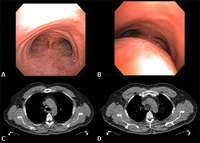

Dynamic airway collapse: A. bronchoscopic view on inhalation; B. bronchoscopic view on exhalation showing dynamic airway collapse; C. CT chest showing normal airway on inhalation; D. CT chest showing significant airway collapse on exhalation

From the collections of Jose Fernando Santacruz MD, FCCP, DAABIP and Erik Folch MD, MSc; used with permission